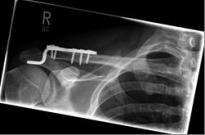

Schlüsselbein 2                  Schlüsselbein 3

Images: A lateral clavicle fracture was treated with a hook plate. The hook is fixed under the acromioclavicular, while screws anchor the plate in the collarbone.